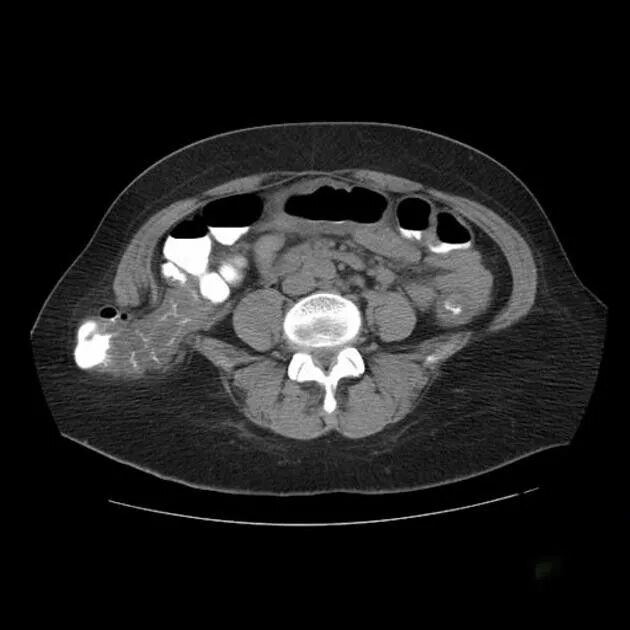

Грыжи на кт